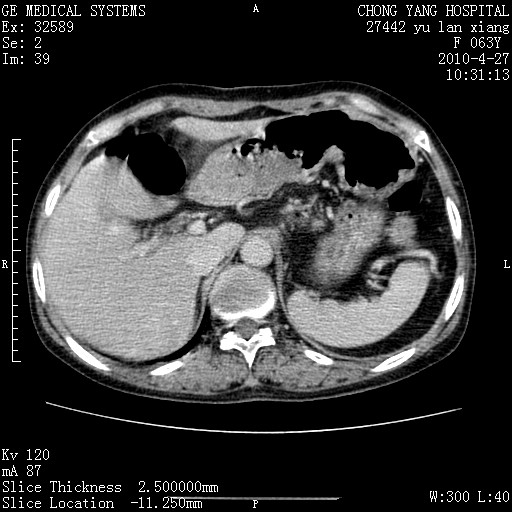

标题: CT26066:F63Y 上腹正中压痛半月,CA199:7400u/ml,MR示胰腺炎伴 [打印本页]

胰腺癌侵犯腹腔动脉干-分支、胃壁、左侧膈肌伴胰周及腹膜后淋巴结转移、胆囊切除术后。

胰腺癌侵犯腹腔动脉干-分支、胃壁、左侧膈肌伴胰周及腹膜后淋巴结转移、胆囊未显影。